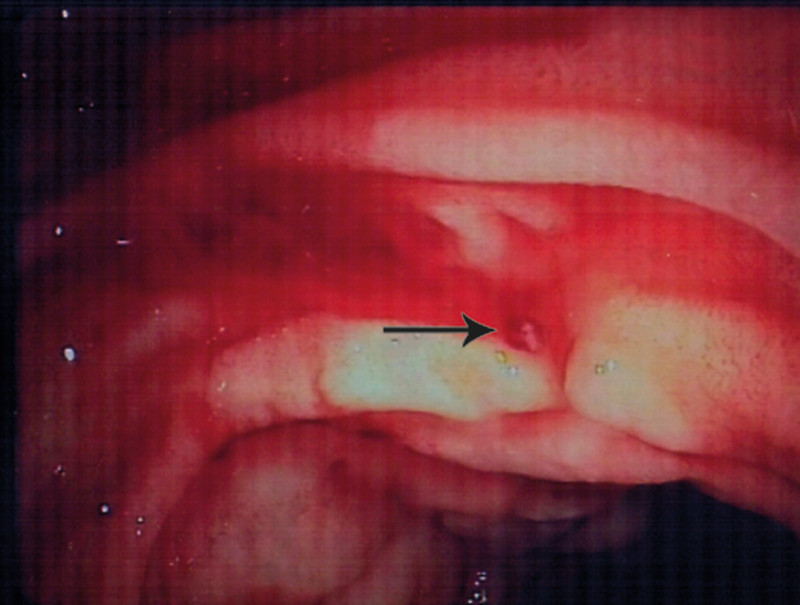

Figure 2  Haemostasis following injection of Aetoxysklerol and application of argon plasma coagulation

Arterial bleeding from a macroscopically normal mucous membrane provided diagnostic clarification. The finding was consistent with Dieulafoy’s lesion (exulceratio simplex), i.e. bleeding from a dilated submucous arteriole.